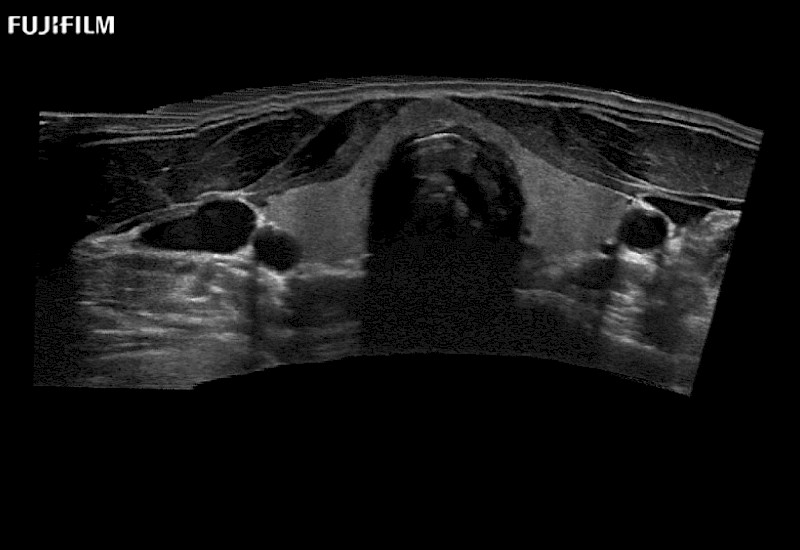

Curved array “T” style finger-grip transducer for open surgical procedures.